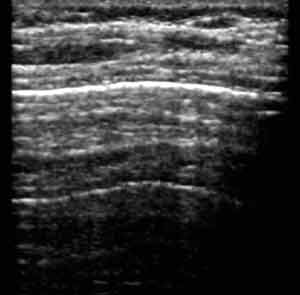

Эхография в диагностике заболеваний легких у детей.